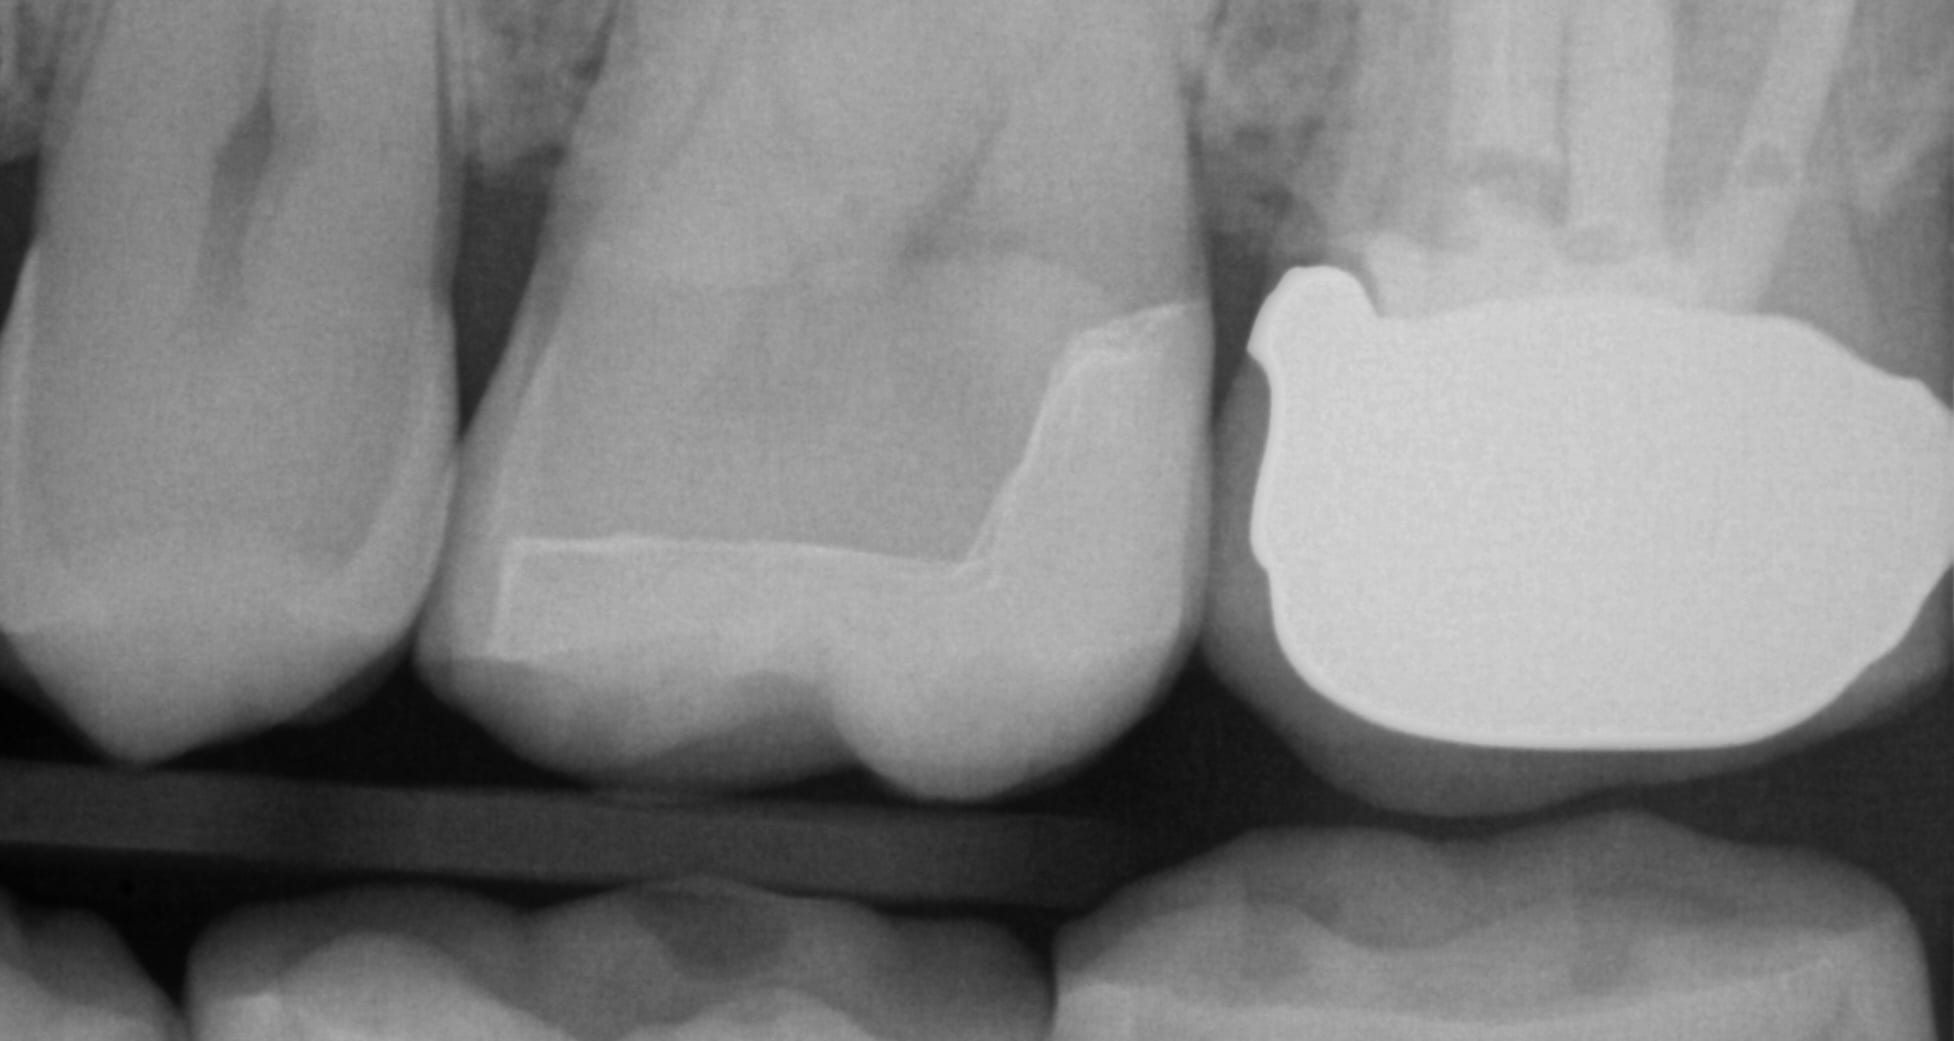

open margin pfm crown Zirconia Crown X Ray when applied the right way, a zirconia crown can improve your overall oral health in a heartbeat. this study aimed to evaluate the clinical efficacy of monolithic zirconia crowns for posterior teeth restorations. This plan will outline the number of crowns needed, the desired shape and color, and any other relevant details. Once the decision is made to. Zirconia Crown X Ray.